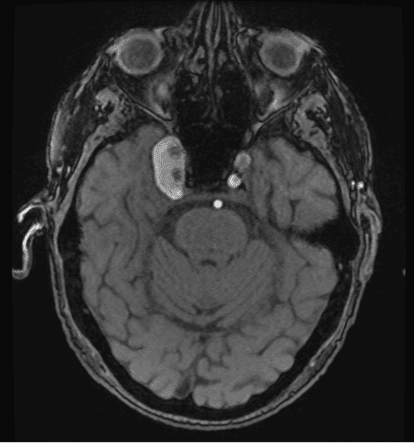

He was urgently referred to neurosurgery, who operated twice on the aneurysm using endographic stenting. After surgery, he was initiated on anticoagulant therapy to include Plavix 75 mg and aspirin 81 mg daily. Post-surgical notes indicated that there was an improvement in oculomotor function and pupillary reaction, and the patient was instructed to follow up every six months with neurosurgery with repeat imaging. One year after his second surgical repair and two months after his follow up with neurosurgery, he returned to the eye clinic. His exam demonstrated completely restricted adduction, which prompted obtaining MRI/MRA urgently, which revealed an increase in size of the CCA to 3.2 cm (Figure 2).

Figure 2. MRA (inferior coronal view) indicating a giant right cavernous segment internal carotid artery aneurysm, status post endographic surgery, measuring 32 mm anteroposterior x 16 mm transverse x 21 mm caudocranial. Incidentally, there was a second left internal carotid artery aneurysm of the cavernous sinus, measuring 7 mm.